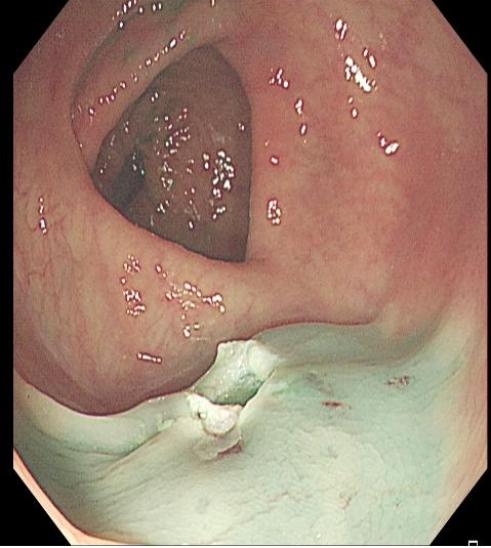

■ IIa-c型病变

对于直径较大的IIa-c型病变及部分Is病变,若直接圈套切除,可能造成全层损伤,通过黏膜下注射液体可增加病变隆起高度,减少圈套和切除难度。而术中是否具备隆起症,又是确定腺瘤良恶性和有无内镜下治疗指征的一个重要依据。此方法能增加直径<2 cm 腺瘤的完整切除率。

上下滑动查看△图4 Ⅱa 型息肉 EMR 治疗流程图。